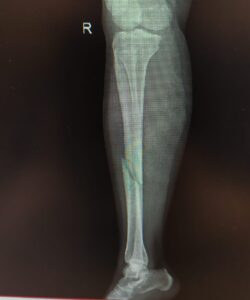

if the fracture is displaced, surgery may be needed to put the bone back into the correct position and fix the bone with Plates & screws or nails for adequate healing to occur.

- Tibia Fractures.